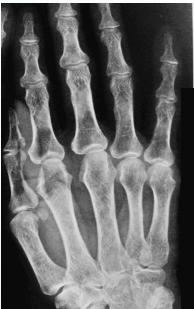

- In hand, sub-periosteal bone resorption .This change usually happen in the middle phalanges, radial aspect in the 2nd or 3rd finger.

Sub-periosteal bone resorption

- Most useful sign

- Virtually Diagnostic

- Location

Subperiosteal bone resorption (straight arrow), resorption of the tip of the terminal phalanx and the altered bone architecture. Arterial calcification is also present (curved arrow).